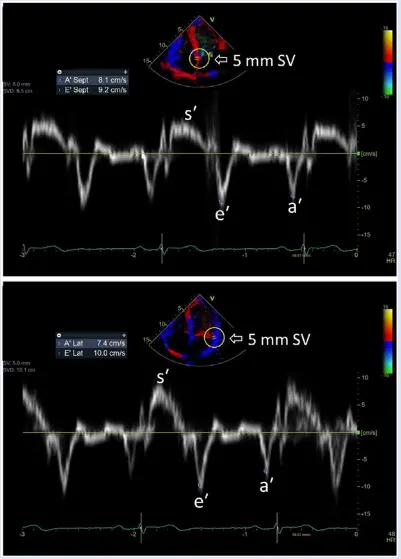

Mitral annular velocity: e’ velocity (cm/s): peak early diastolic modal velocity after ECG T-wave

Mitral annular velocity: a’ velocity (cm/s): peak late diastolic modal velocity after ECG P-wave

As a general rule of thumb, normal LV relaxation is suggested by medial e’ ≥ 9 cm/s and lateral e’ ≥ 12 cm/s. However, values can vary by age 👇

- According to Dr. Oh, e’ velocity is money 💵 because normal LV relaxation (e’) means you must have normal diastolic function. This is reflected in the Step 1→Step 2 algorithm (Figure 2) proposed in the 2025 guideline update.4

- In other words, you can stop looking for other markers of diastolic dysfunction if you have normal e’ velocities.

- “Once you see that e’ is normal, you don’t need to look at anything else because you cannot have diastolic dysfunction with normal e’ velocities” - Dr. Oh

- “Normal e′ velocity is unusual in patients with diastolic dysfunction related to a myocardial abnormality or disease, which is a main reason that the joint Diastology Working Group recommends that an evaluation of diastolic function begins with e′ in patients with normal LV ejection fraction.” 3

- In healthy hearts, a significant amount of LV ejection and LA filling results from descent of the mitral annulus toward the apex. This longitudinal motion normally precedes filling.1

- A bunch of comorbidities (e.g., HTN, obesity, diabetes) can lead to impaired myocardial relaxation and restoration forces, and ↑ lengthening load (LA pressure) → reduced and delayed longitudinal motion and e′ velocity